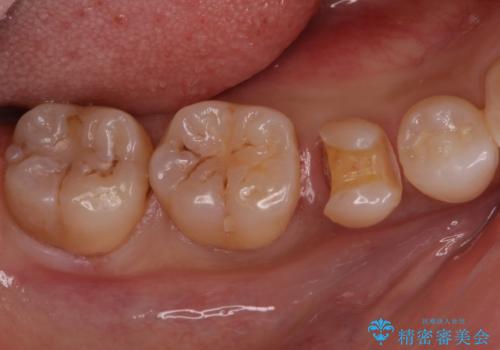

歯と歯の間の虫歯 セラミックインレーでの修復処置

- 検査の結果、歯と歯の間に虫歯が確認された患者様です。

虫歯を除去した後、セラミックインレーで修復処置を行います。

- 右下5 セラミックインレー 77,000円費用は治療当時の料金となります

レントゲン画像では写りにくい小さな虫歯も発見したため、そこも含めた形での修復処置を行いました。